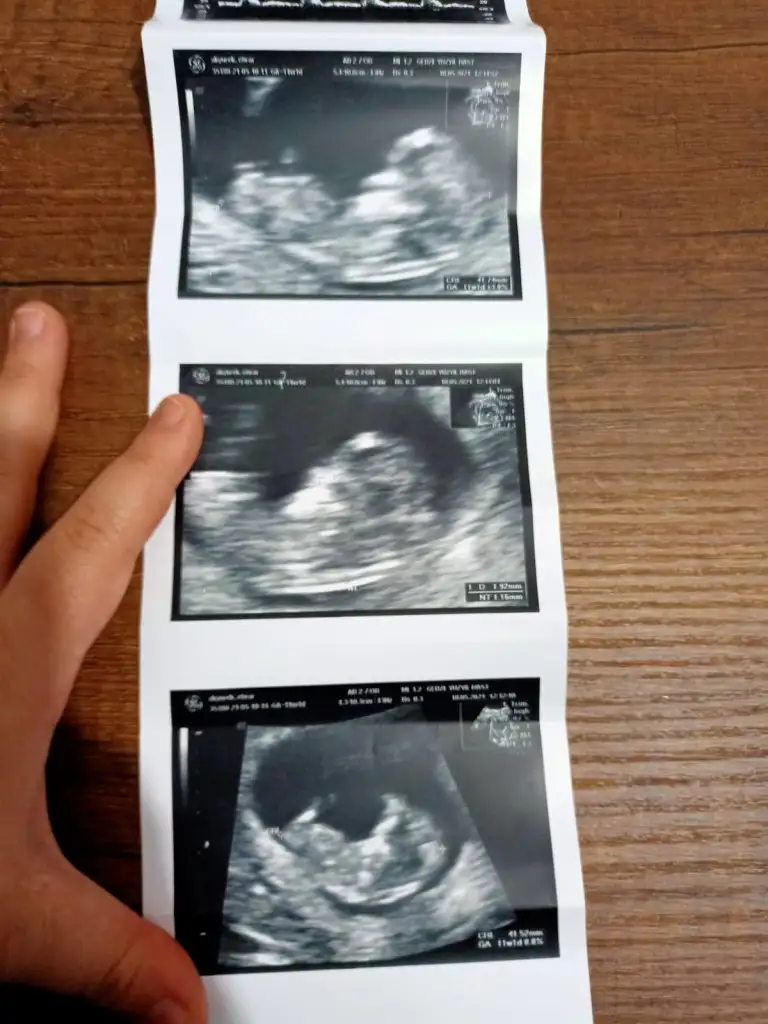

Emin olmadım ama sanki kız gibi geldi banaMerhaba arkadaslar,aslinda bebegimin cinsiyeti belli,dr.eşime kağıda yazıp verdi ama eşim pazar gunu surpriz yapacagi icin bana søylemiyor,sizin bi tahmininiz varmı?Merakdan çatliyorum.Eki Görüntüle 2848569

Valla bravo arkadaşım,az ønce øgrendim, Allahin izniyle zillim geliyorEmin olmadım ama sanki kız gibi geldi banaen iyi 11 12 13 haftalar olmalı yada başka USG varsa paylaşın

Anketimi oylarsaniz sevinirim sağlıkla gelsin prensesIkra hanım merhaba 11+1den karından usg atıyorum rica etsem tahminde bulunur musunuz arkadaşım için bana kız demiştiniz doğru cıktı

Erkek görünüyorIkra hanım merhaba 11+1den karından usg atıyorum rica etsem tahminde bulunur musunuz arkadaşım için bana kız demiştiniz doğru cıktı

Kız diyecem ama emin olamadım

Bir de benimkine baksanız olur muEmin olmadım ama sanki kız gibi geldi banaen iyi 11 12 13 haftalar olmalı yada başka USG varsa paylaşın